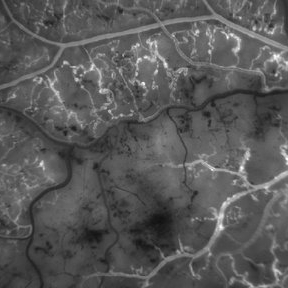

Retinitis Pigmentosa With Hemangioma CF

Dec 15 2016 by Manish Nagpal, MD, FRCS (UK), FASRS

Fluorescein angiography OS of a patient having retinitis pigmentosa with a hemangioma inferiorly.

Condition/keywords: hemangioma, retinitis pigmentosa